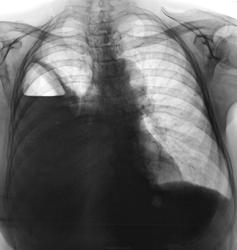

Контроль после лечения в Х.О.

1.dscn0287.jpg2.dscn0287a.jpg3.dscn0288.jpg4.dscn0288a.jpg

Эффект дренирования неоспорим, но - полость сохраняется, и самое главное - а что в пунктате?...неужели - соломенно-желтая?))))

В пунктате - гной